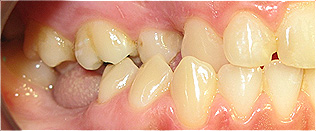

Apinhamento dentário com os dentes caninos em desoclusão (classe II, divisão 2).

![]() |

Após dois anos de tratamento ortodôntico.